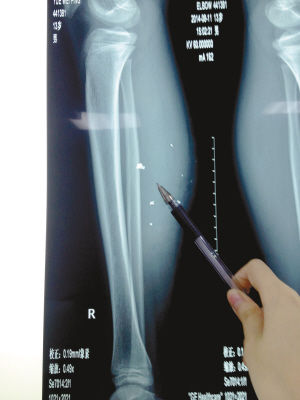

X光片顯示:手機電池內(nèi)的物質(zhì)被炸進了小平的右小腿里

8月10日凌晨,小平轉(zhuǎn)院至重慶醫(yī)科大學(xué)附屬兒童醫(yī)院。小平的主治醫(yī)生骨科二病房周悅航醫(yī)生介紹,入院時小平右小腿腫脹,經(jīng)檢查,發(fā)現(xiàn)有爆炸傷伴異物殘留。傷口較深,約1.5厘米~2厘米,手機爆炸后進入患兒小腿的異物約有10處。周悅航說,由于進入皮膚的異物較多,已深入肌肉,且比較分散,最深的一塊貼近骨頭,可能需要多次手術(shù)。

另外,醫(yī)生擔(dān)心手機爆炸后金屬物進入患兒體內(nèi)可能會對患兒肌肉造成損傷,所以需盡快手術(shù)。據(jù)悉,8月14日上午,小平將接受小腿爆炸傷清創(chuàng)與異物取出術(shù)。